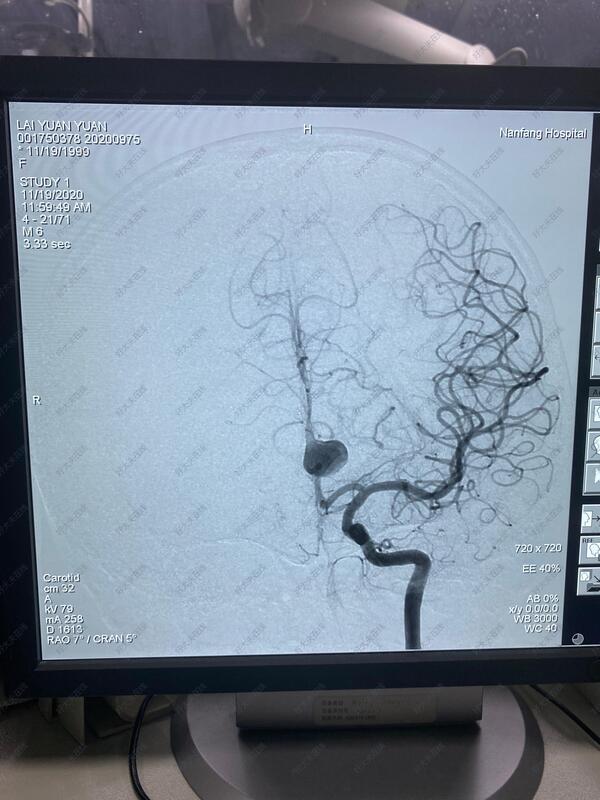

治疗前

21岁年轻女性,头痛检查发现左侧大脑前动脉A2段大型动脉瘤,植入密网支架重建血流,以达到修复血管,治愈动脉瘤的目的